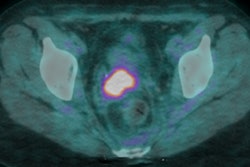

Key indicators to help radiologists differentiate between benign and malignant peripheral nerve sheath tumors in patients with and without neurofibromatosis included the size of the lesion, growth rate, expansion into adjacent areas, and maximum standard uptake values (SUVmax).

All of the subjects had undergone MRI and/or PET/CT scans prior to surgery between 2009 and 2016. MRI scans were used to assess the size, location, and growth of the tumors, as well as their necrotic content or hemorrhage and surrounding edema. PET/CT was used to calculate the SUVmax of each lesion.

PET/CT achieved high sensitivity and specificity for diagnosing malignant neurofibromas within certain SUV ranges (mean SUVmax value, 5.09; SUVmax range, 3.77-6.35). With MRI, a high T1 signal was indicative of a malignant tumor (p = 0.006), while a high T2 signal (p = 0.05) and a hypointense tumor center (p = 0.034) were more indicative of benign tumors.